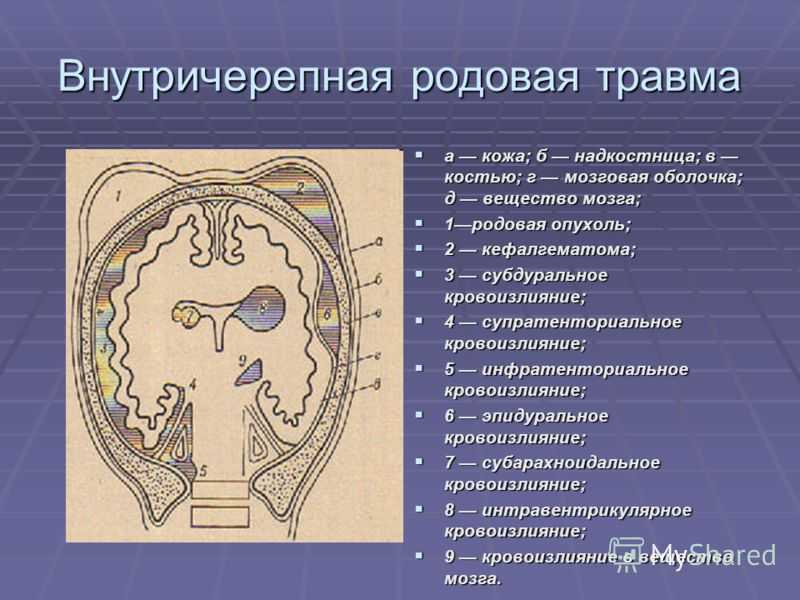

Внутричерепные кровоизлияния у новорожденных презентация - 92 фото